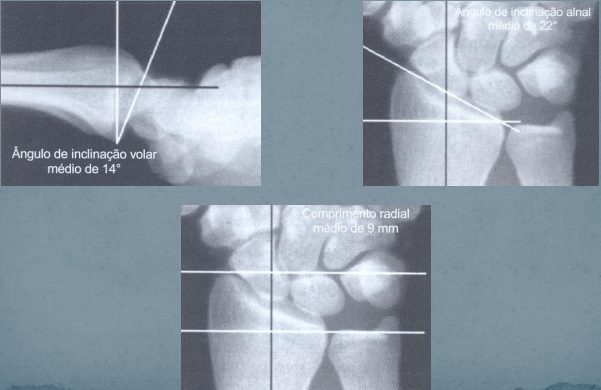

– A superfície articular do rádio possui, em média, 14° de inclinação

volar e de 22° de inclinação ulnar e o comprimento do rádio é de

9mm